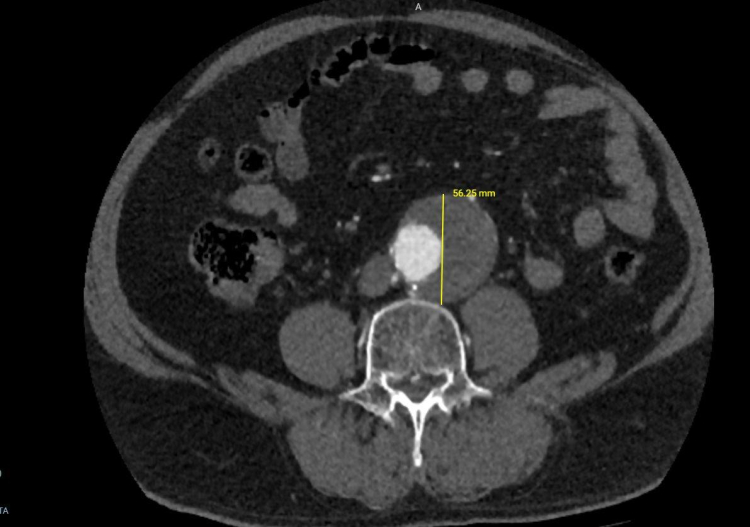

Karın aort anevrizması, vücudun en büyük atardamarı olan aortun karın bölgesindeki kısmının anormal şekilde genişlemesidir. Kontrol altına alınmadığında, bu genişleme yırtılma (diseksiyon) riskini beraberinde getirir ki bu da hayati tehlike taşıyan bir durumdur. Hastanın aort damarındaki genişlemenin 56 mm'ye ulaşması üzerine, bu potansiyel patlama riskini ortadan kaldırmak amacıyla EVAR prosedürü uygulandı.